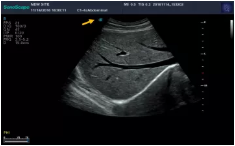

Mark點:每一把探頭都有一個mark點,是用于定位方向, mark點一側始終對應著圖像S點(圖像箭頭標識)一側。